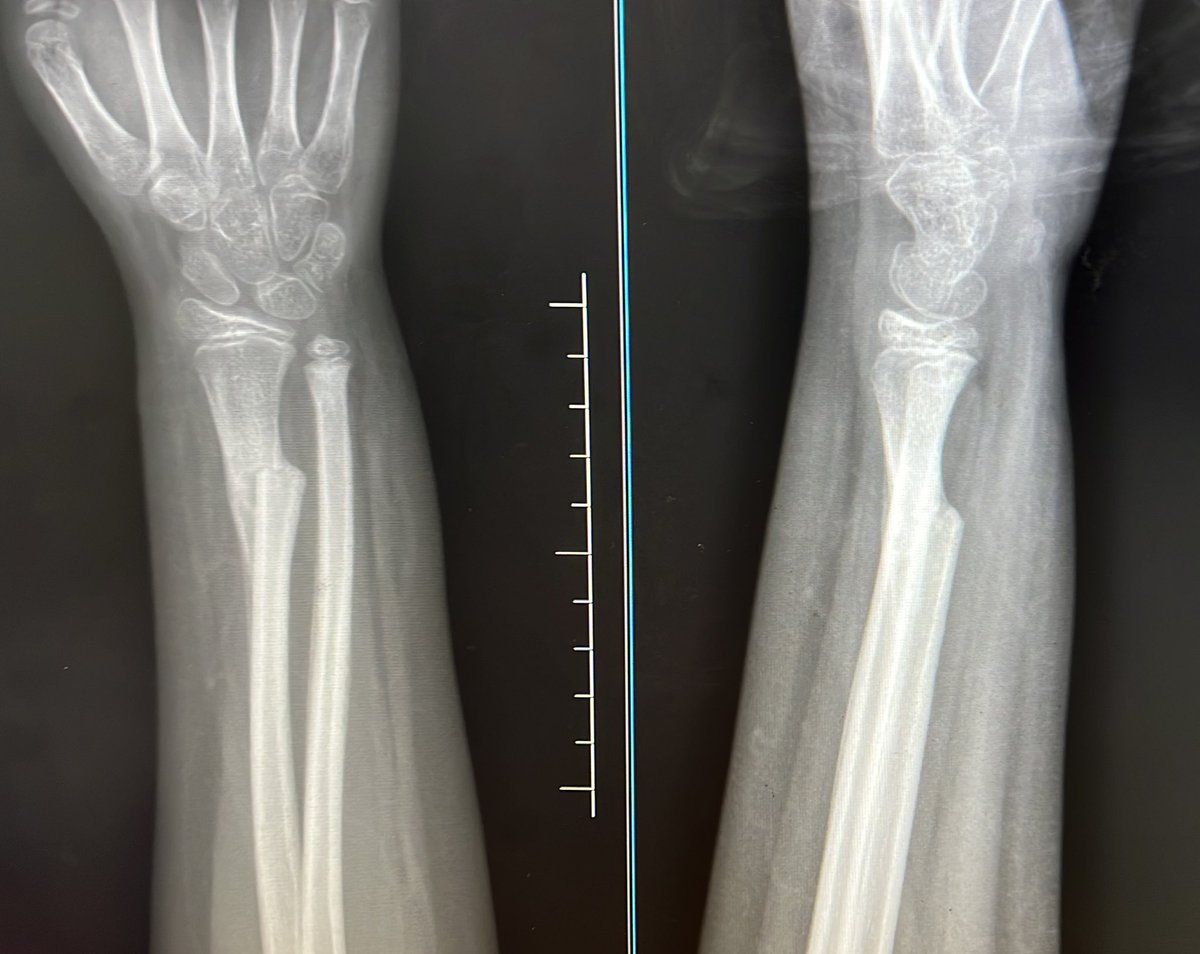

Patients who had symmetric tibial augment constructs exhibited similar rates of radiolucency but higher survivorship compared to those with asymmetric constructs overall. However, when metaphyseal cones were utilized, survivorship was equivalent. https://t.co/ForMz4dU8s